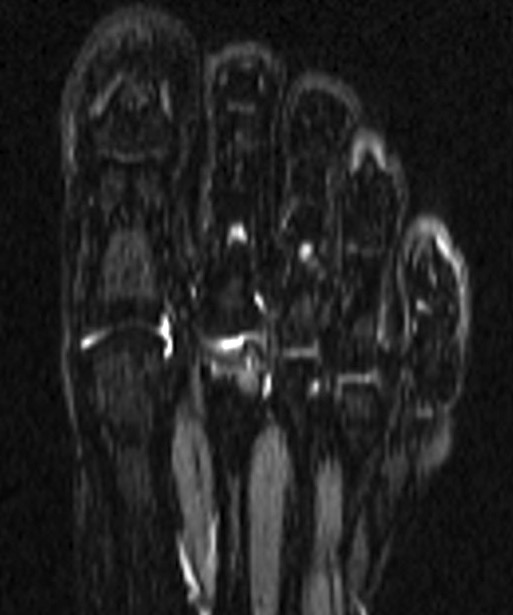

MRI